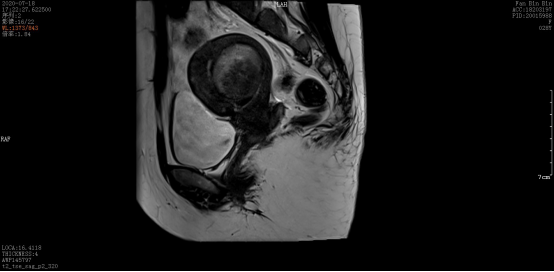

术后:

微波消融后肌瘤病灶内会发生凝固性坏死,即刻超声造影就可以看到病灶内没有造影剂充填。磁共振增强扫描病灶内呈现充盈缺损,增强后呈黑色区域,表示病灶坏死区域。坏死的病灶随时间推移,会逐渐萎缩吸收,子宫体积也会有一定的缩小,从而使痛经、月经量多等临床症状得到缓解和改善。